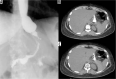

Material and methods: We retrospectively review 954 obese patients who underwent bariatric surgery between 2013 and 2019. The study included 72 patients who developed clinical suspicion of acute complications (painful and meteoric abdomen, nausea, vomiting, fever, intestinal blockage) within 6 days of bariatric surgery of sleeve gastrectomy, gastric banding, gastric bypass with Roux loop confirmed by CT, and who underwent a gastrointestinal transit before the CT examination.

Results: GI exam allowed visualisation of 58% of complications. Analysing the data for each surgical technique, 46 post-operative complications were found involve gastric banding. The most frequent was bandage migration (26 cases, 56 %), identified in all cases at GI transit and then confirmed on CT.